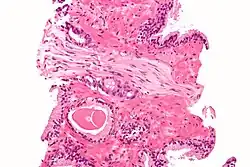

As fibras nervosas que formam o nervo são sustentadas e protegidas por três revestimentos de tecido conjuntivo: endoneuro, tecido conjuntivo delicado que circunda imediatamente as células do neurolema e os axônios. Perineuro é uma camada de tecido conjuntivo denso que envolve um fascículo de fibras nervosas periféricas, proporcionando uma barreira efetiva contra a penetração das fibras nervosas por substâncias estranhas. Epineuro é uma bainha de tecido conjuntivo espesso que circunda e encerra um feixe de fascículos, formando o revestimento mais externo do nervo; inclui tecido adiposo, vasos sanguíneos e linfáticos. Dentro do endoneuro, as fibras nervosas individuais são cercadas por um líquido de baixa proteína chamado fluido endoneural.[1] Este age de forma semelhante ao líquido cefalorraquidiano no sistema nervoso central e constitui uma barreira nervo-sanguínea semelhante à barreira hematoencefálica.[2] As moléculas são assim impedidas de cruzar o sangue para o fluido endoneural. Durante o desenvolvimento de edema nervoso por irritação nervosa ou (lesão), a quantidade de líquido endoneural pode aumentar no local da irritação. Este aumento no flúido pode ser visualizado através de imagens de ressonância magnética.

Os nervos são organizados como um cabo telefônico: os axônios assemelham-se a fios individuais isolados pelo neurolema e endoneuro; os fios isolados são reunidos pelo perineuro e os feixes são circundados pelo epineuro, que forma o revestimento externo do cabo. É importante distinguir entre fibras nervosas e nervos, que às vezes são representados como sendo uma única e mesma coisa.[1]